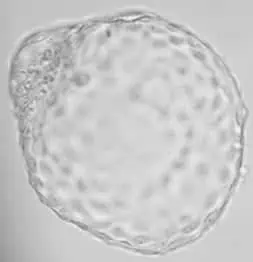

Transferujeme opravdu kvalitní embrya

Genea jako první zavedla transfer embryí ve stádiu blastocysty. Dobře provedená prodloužená kultivace umožňuje získat kvalitní embrya, která mají vždy vyšší šanci na úspěch než 3denní. 5denní kultivace optimálně kopíruje ženin přirozený cyklus. Umožňuje vkládat do dělohy embrya stejně stará, jako v nativních cyklech. 3denní embryo do dělohy prostě nepatří.